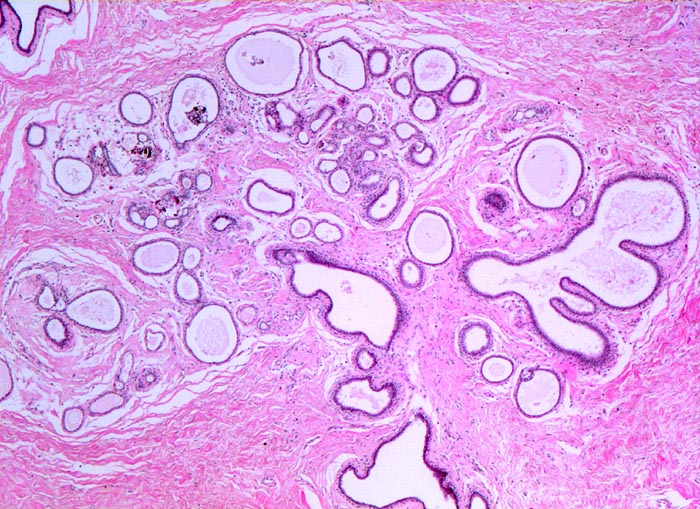

Ausgeprägte Fibrose und zystisch erweiterte Gangstrukturen in organoider Anordnung.

Im Zentrum des Präparates stark erweiterte Gänge mit intraduktalen peripheren Papillomen.

Alle Drüsen zeigen eine erhaltene äussere abgeflachte Myoepithelschicht mit hellem Zytoplasma.